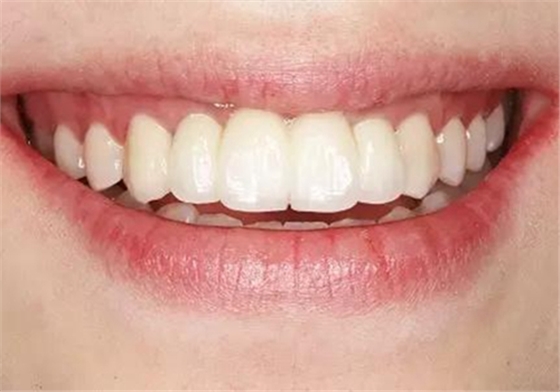

圖37 戴入全瓷修復(fù)體局部舌側(cè)觀 圖38 永久修復(fù)后微笑

圖39 永久修復(fù)后大笑